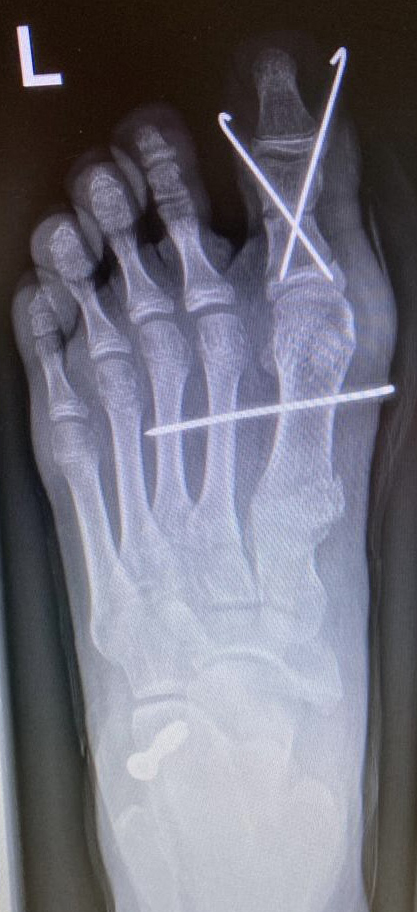

Zusätzlich schränken Wachstumsfugen die Wahl der Osteosynthese ein. Eine die Fuge kreuzende Osteosynthese ist ausschließlich mit Kirschner-Drähten möglich (Abb. 3).

Abb. 3 a-j: Beispiel einer Calcaneusverschiebeosteotomie mit offenen Wachstumsfugen und der entsprechenden Osteosynthese mit Kirschner Drähten. Lokalisation der Osteotomie (a), Lage der Fräse (b-d), Drahtlage mehrere Ansichten (e-h), Heilung der Osteotomie 4 Wochen postoperativ und Entfernung der Drähte (i-j).

Zum Lesen der Bildbeschreibung und zur Vollansicht bitte die Bilder anklicken. Bilder: A. Helmers.